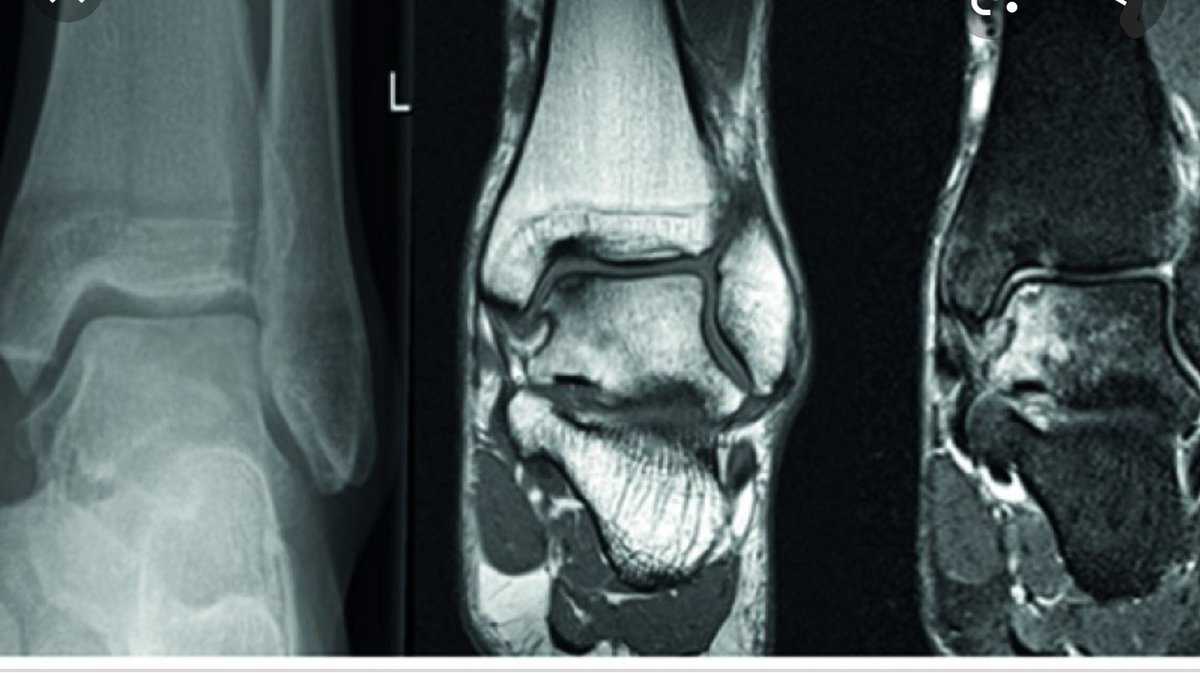

الأشعة:

التشخيص يكون عن طريق أشعة الرنين المغناطيسي